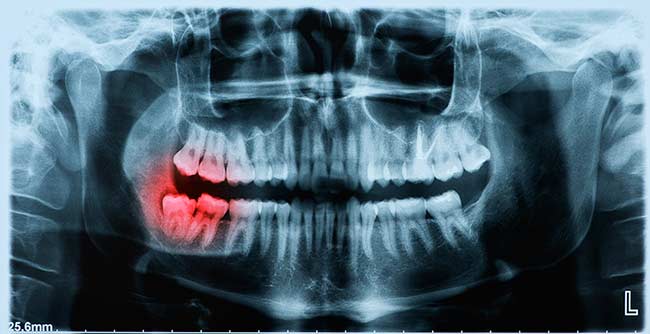

The process begins when a 3D scan is taken of the patient’s jaw bone. This 3D scan allows for the generation of a three-dimensional model of the jaw bone that can then be used with digital software to plan the implant placement without the presence of the patient. The results are a more accurate implant placement and less chair time for the patient.